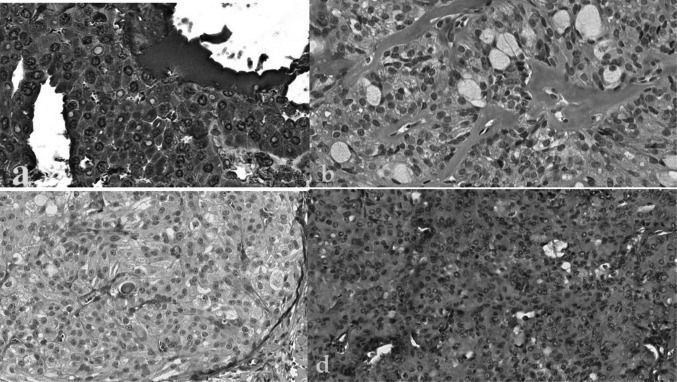

Materials and methods: Forty well-investigated parotid MEC cases (p63+, p40+, CK7+, Ck5/6+, AE1/AE3+, EMA+, S100 -, ATF1 -, WT1-, SOX9 - and SOX10 -), all with MAML2 rearrangements and without EWSR1 alteration, were interrogated using immunohistochemical techniques to detect the immunoreactivity for Nanog, SOX2, OCT4, and MENA. Additionally, the POU5F1 FISH probe was used to confirm the immunohistochemical findings for OCT4.

Results: Immunohistochemical analysis revealed negative or nonspecific immunoreactivity of NANOG, SOX2, and OCT4 antibodies throughout all examined specimens, inferring deficient pluripotency factor within MEC cellular oncogenesis. However, MENA was widely expressed in all cases. The results of the POU5 F1 FISH probe were consistent with the immunohistochemical data, showing no detectable expression of OCT4, Nanog or SOX2, across all 40 samples.